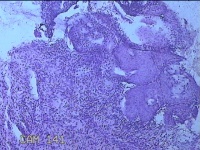

宫颈6点、12点组织

性别

女

年龄

33岁

临床诊断

人乳头瘤病毒感染

一般病史

发现HPV18,其他12种阳性近一月。

标本名称

大体所见

1.“宫颈6点组织”:灰白粉红色组织0.5x0.3x0.2cm一块。 2.“宫颈7点组织”:灰白暗红色组织0.8x0.3x0.2cm两块。

图4